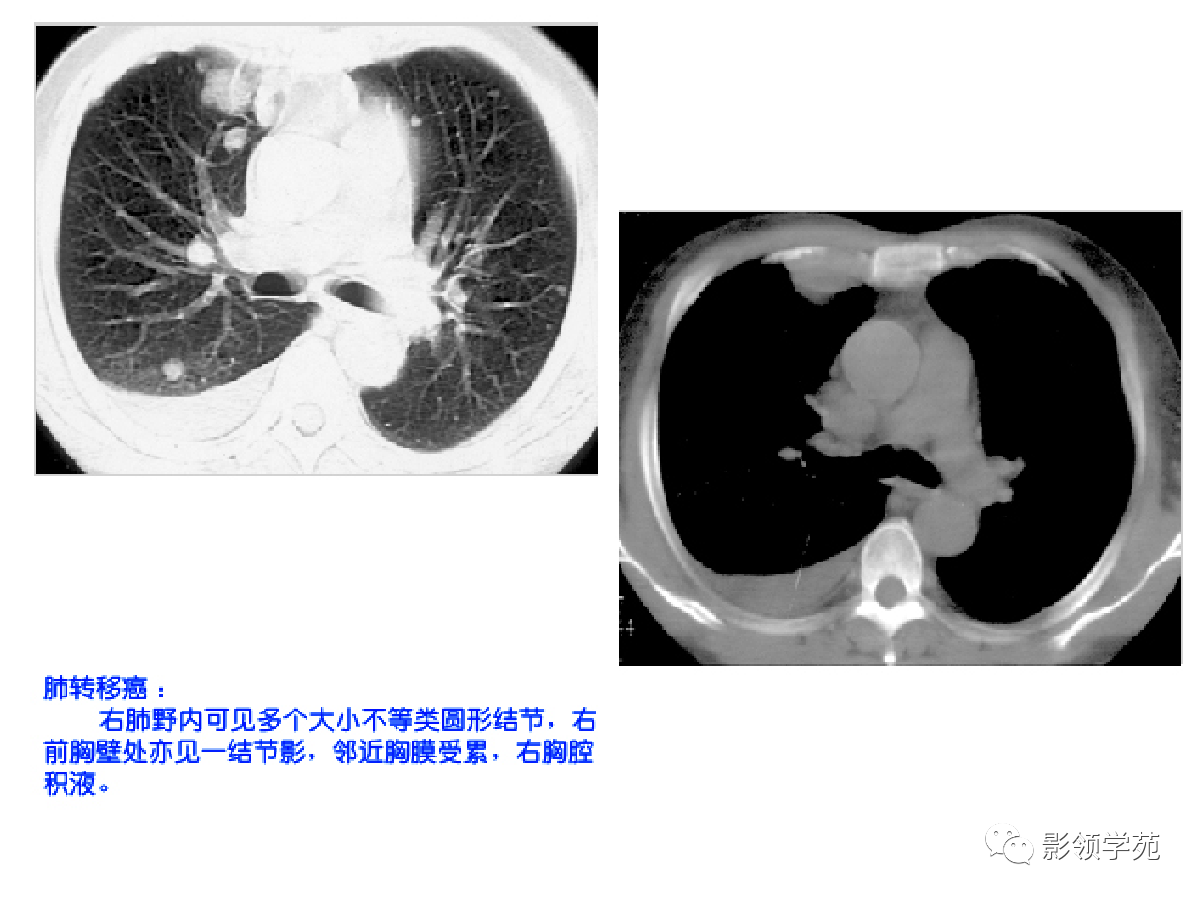

多发或单发结节,大小不一,边缘较清楚。少数结节伴出血时出现晕轮征,即有略高密度影像环绕结节,使病变边缘模糊。病变有钙化常见于骨肉瘤或软骨肉瘤转移。转移瘤亦可表现为空洞。两肺多发的小结节影具有随机分布的特点,HRCT显示结节位于小叶中心、小叶间隔、支气管血管束及胸膜,结节大小不均匀。

肺转移瘤。肺窗像(A)示双肺野可见大小不等的圆形高密度结节影,纵隔增宽;纵隔窗像(B)示肺内肿块呈实性,纵隔满布大小不等的肿大淋巴结